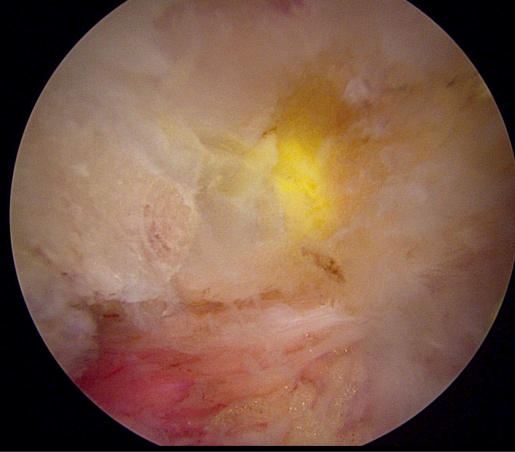

양방향 척추 내시경을 통한 다발성 척추 협착증의 치료 [온종합병원 척추센터 우영하 소장 ]

척추관 협착증은 척추관이 좁아지거나 협착되어 척수나 신경근을 압박하는 상태를 말합니다. 이런 경우, 양방향 척추 내시경이 매우 유용한 치료 수단이 될 수 있습니다.

- 계획: 양방향 척추 내시경은 미세한 카메라와 도구를 사용하여 척수와 주변 신경 구조를 정밀하게 시각화할 수 있습니다. 이를 통해 정확한 진단을 내릴 수 있으며, 각 환자에게 맞는 개별적인 수술 계획을 수립할 수 있습니다.